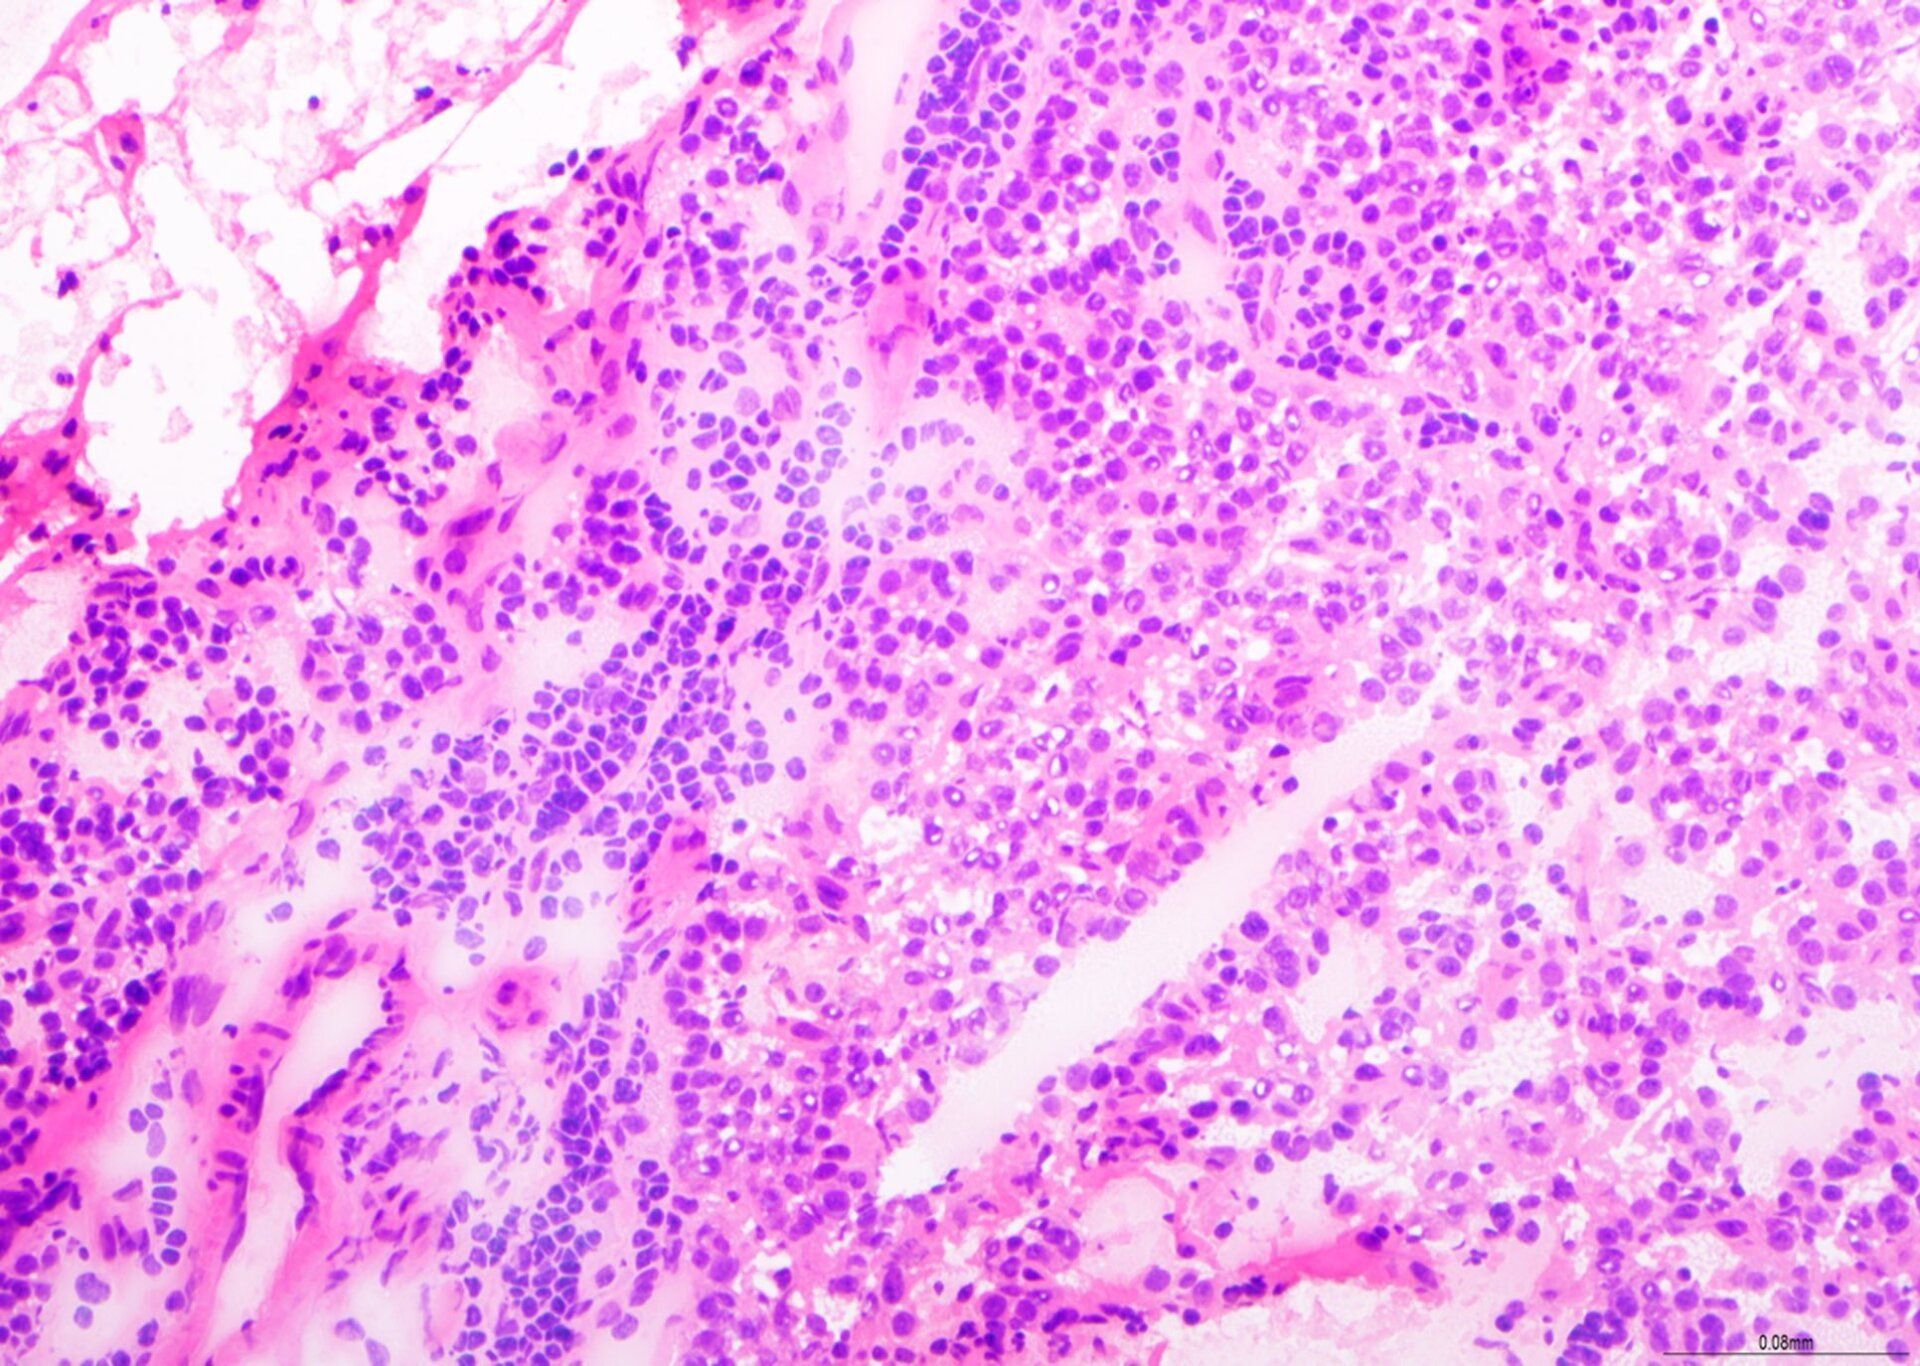

Schema H&E - BMT

Si tratta di un'eccellente preparazione per una biopsia del midollo osseo (BMT), con colorazione H&E bilanciata, buon dettaglio della cromatina e colorazione selettiva dei tipi cellulari all'interno del tessuto midollare. Questo vetrino ha ottenuto un punteggio di 9/10 in fase di valutazione.